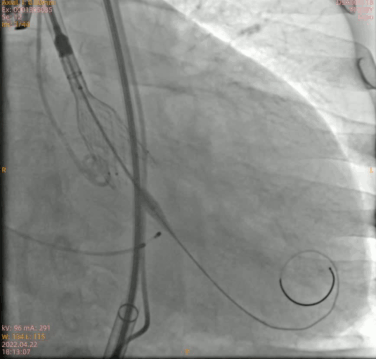

定位

瓣膜三分之二造影